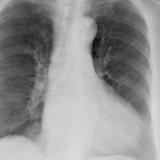

Case 8a Thymoma PA

Date: 03/27/2009

Views: 9539